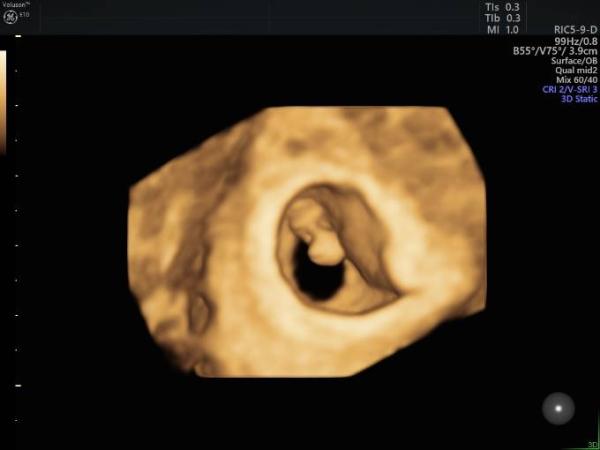

Wie schön es doch ist, das erste mal den Herzschlag zu hören. Das macht das Ganze so viel realer! Es war wirklich ein toller Moment! Heute war es nur ein kurzer Termin und 11 Tagen gibt es dann den größeren Termin mit Mutterpassübergabe. Hier mal zur Abwechslung ein Ultraschallbild in 3D :) Viel ist aber noch nicht zu erkennen....

Bild zu Auch 1. FA Termin - Forum für Januar - Mamis

Mensch toll das mal in 3D zu sehen, da kann ich es bei mir auch gleich viel besser vorstellen! Toll das du so einen schönen Termin hattest, ich schwelge gerade selbst auf dem frisch-erleichtert-vom-Arzttermin Gefühl noch

Cooles Bild! Gratulation! Und wenn ich das richtig deute, liegt die Plazenta rechts... Wenn ich mich an den Beitrag zur Ramzi-Theorie weiter unten erinnere, wird es dann wohl ein Junge Außer, das Bild ist über die Bauchdecke und spiegelverkehrt, dann wäre es ein Mädchen

Echt in der 7 SSW konnte man schon das herzle hören uiii! Tolles Bild,hab auch in der 7 SSW meinen Termin ,hoffe ist auch alles gut :) Alles gute